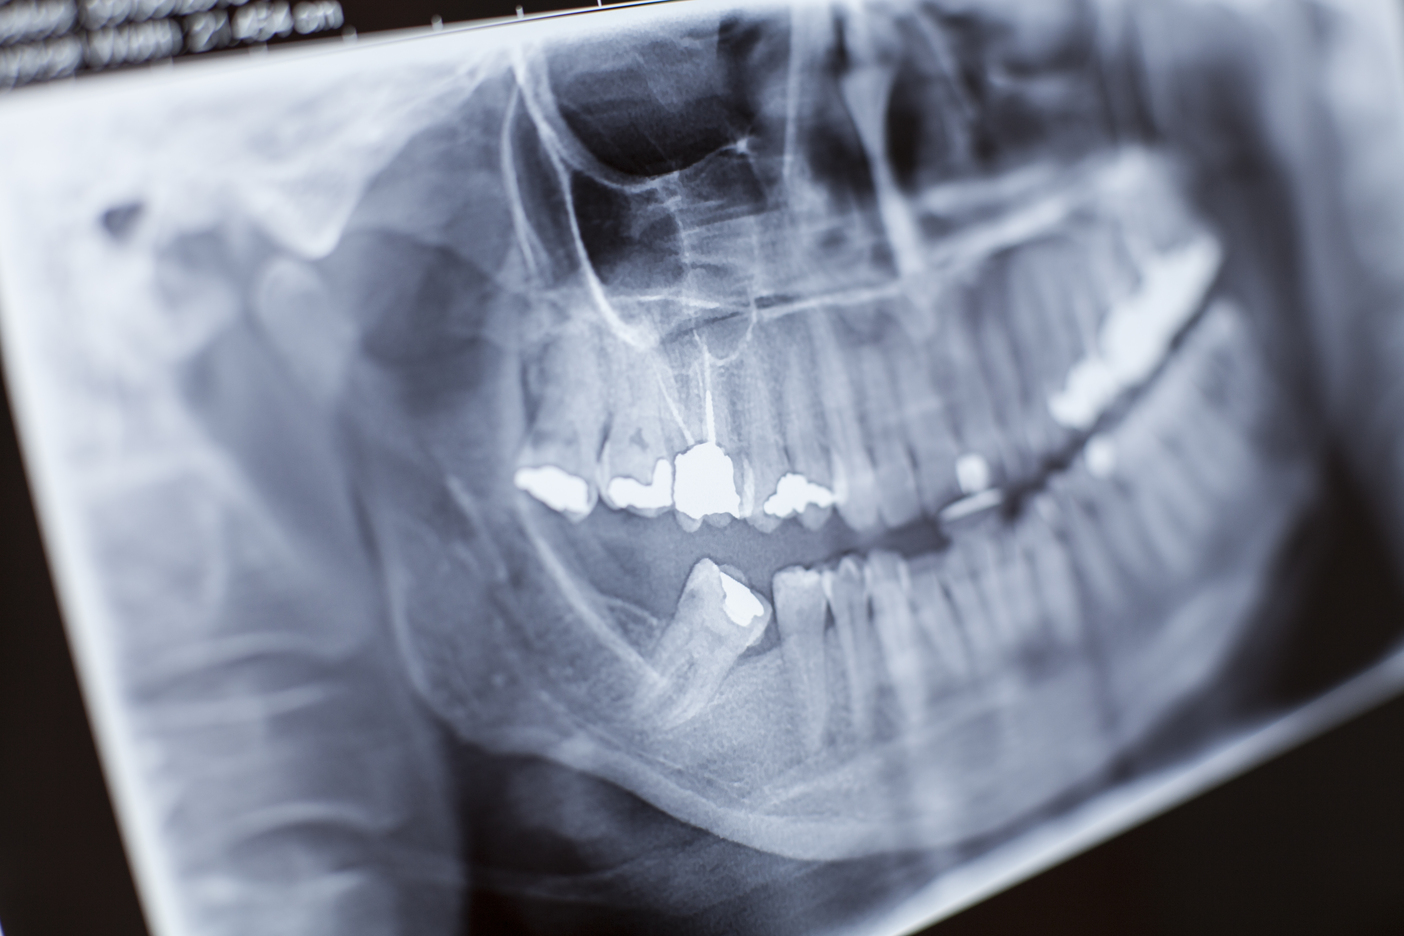

Từ năm 1985 với nhân sự chỉ gồm 1 bác sĩ, 1 kỹ thuật viên và một máy X-quang đơn giản, Khoa Chẩn đoán Hình ảnh đã vượt qua khó khăn nhờ tinh thần đoàn kết. Đến nay, khoa đã phát triển thành một đơn vị chuyên nghiệp với trang thiết bị hiện đại như máy CT Scanner đa lát cắt, hệ thống DR và PACS. Đặc biệt, trong năm 2025, Bệnh viện đã trang bị thêm máy chụp CT ConeBeam Planmeca Viso G7, giúp khảo sát rõ hơn các bệnh lý chuyên ngành Răng Hàm Mặt, hỗ trợ tích cực trong công tác chẩn đoán và điều trị. Năm 2024, khoa đã phục vụ hơn 141.000 lượt bệnh nhân, góp phần nâng cao chất lượng khám chữa bệnh.